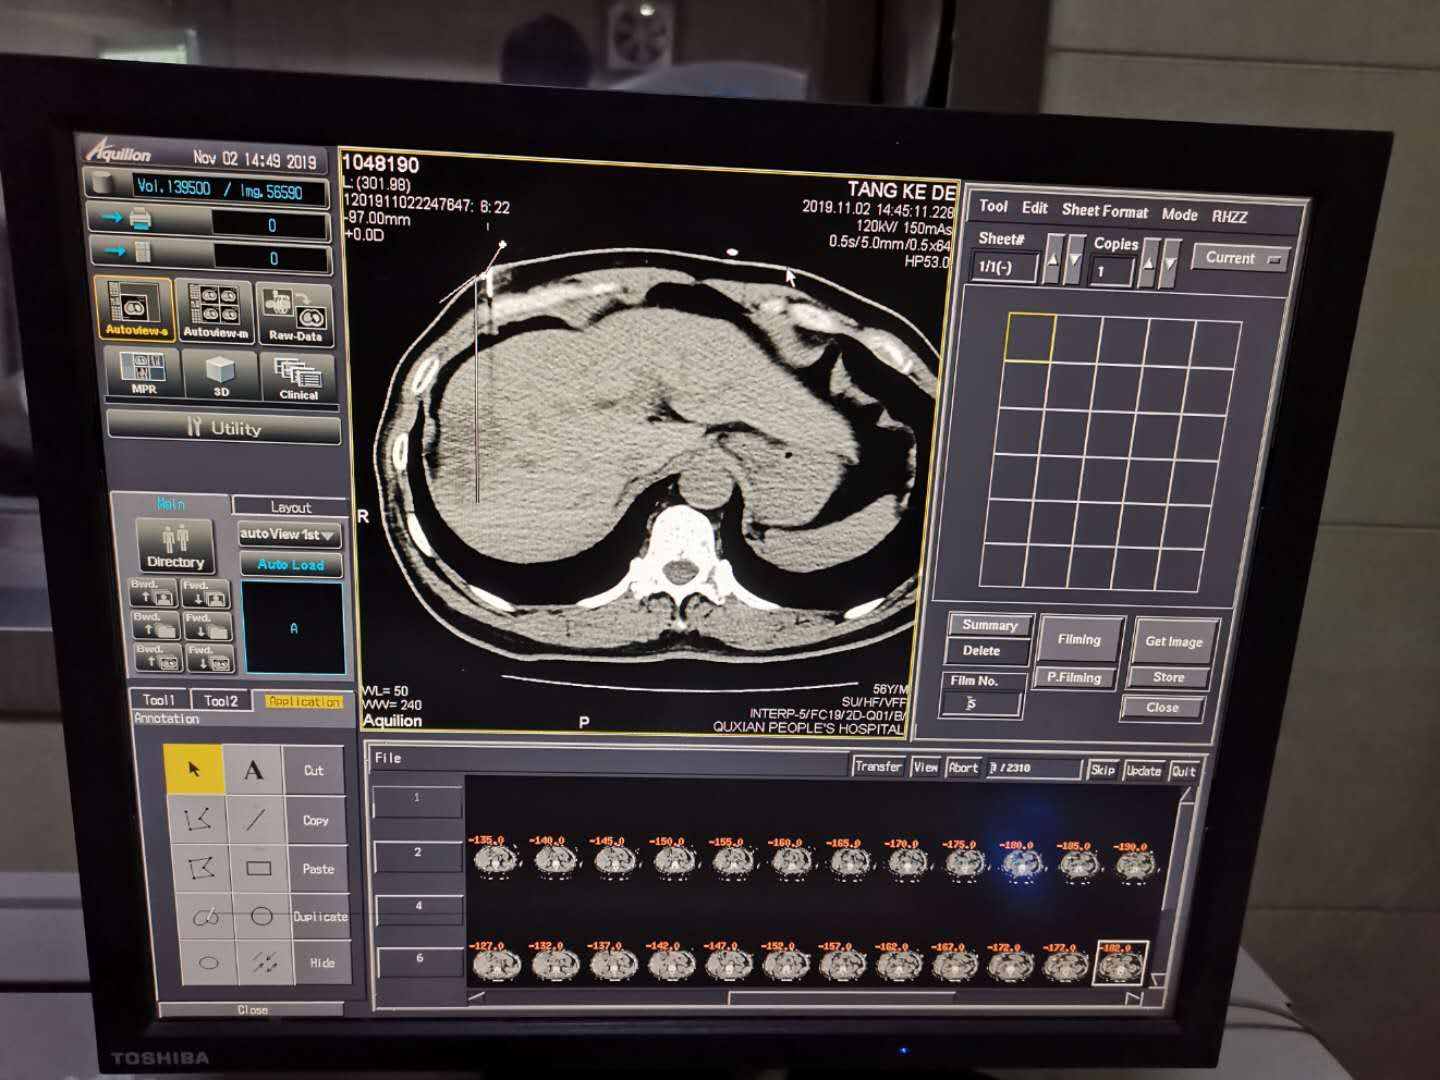

在我院接受该手术的首例患者唐某某,是一位56岁的中年男性,因上腹部不适行腹部增强CT检查发现肝癌,于重庆西南医院完善检查后,确定无外科手术机会,故口服阿帕替尼靶向治疗 ,遗憾的是,5个月治疗后复查,显示病灶增大。于是选择“康博刀”冷冻消融术,该手术不需要麻醉科医师参与麻醉。提起手术过程的感受,该患者表示在整个手术过程中基本无不适感,手术时间短,术后伤口不适感不明显。